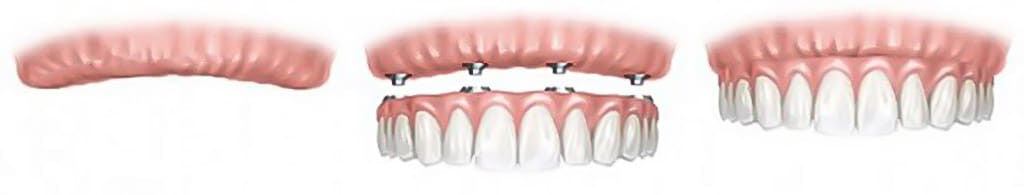

All-on‑4 Zahnimplantate sind eine moderne Technik, die es ermöglicht, eine komplette Zahnreihe mit nur vier Implantaten zu ersetzen. Diese Methode wurde entwickelt, um Patienten eine fest sitzende und stabile Lösung für zahnlose Kiefer zu bieten, ohne dass für jeden Zahn ein einzelnes Implantat erforderlich ist.

All-on‑4 bezeichnet ein Implantatsystem, bei dem eine komplette Zahnreihe auf lediglich vier strategisch platzierten Implantaten befestigt wird. Zwei Implantate werden gerade im vorderen Kieferbereich eingesetzt, zwei weitere in einem Winkel im hinteren Bereich — so wird maximale Stabilität auch bei geringerem Knochenangebot erreicht.

Ja, in der Regel. Nach der Implantation wird noch am Behandlungstag eine provisorische, fest sitzende Zahnreihe eingesetzt, mit der Sie sofort essen und sprechen können. Nach der Einheilphase von drei bis sechs Monaten wird der endgültige Zahnersatz angepasst.